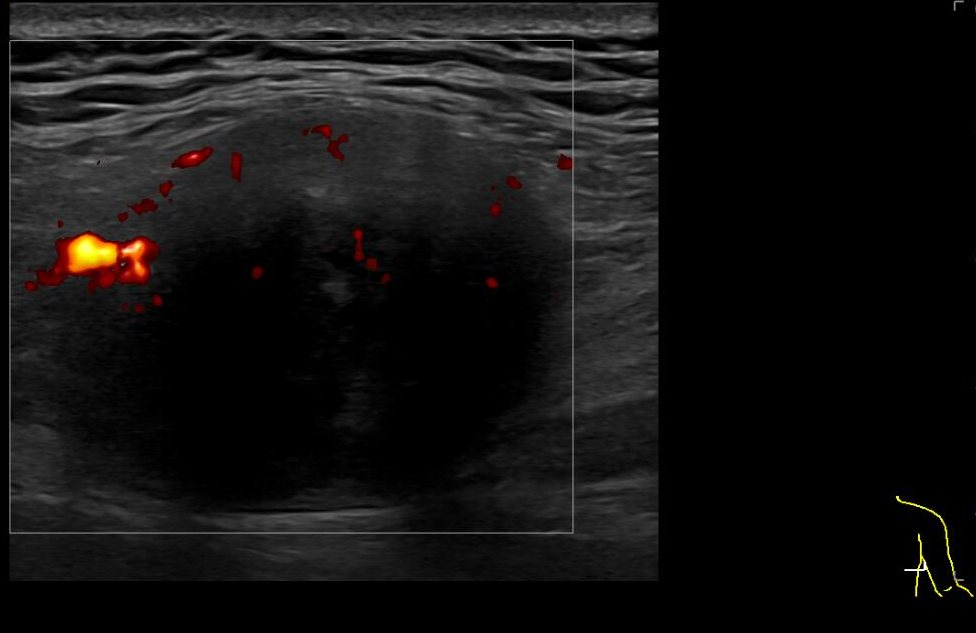

Ecografía: en el tercio medio y posterolateral de la pared torácica derecha, se observa una tumoración sólida, con densidad de partes blandas a nivel más craneal y un componente graso heterogéneo en el polo inferior, de aproximadamente 40 x 32 x 53 mm (transversal-AP-craneocaudal) que presenta pequeños vasos en su interior. Se sitúa en la en el plano muscular superficial, aproximadamente a 7 mm de profundidad respecto a la piel.